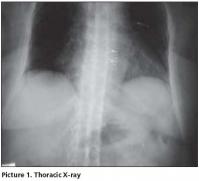

Her postero-anterior chest x-ray was evaluated as normal. In thoracic (Picture 1) and lumbosacral (Picture 2) graphs, marked squaring in her vertebras, shiny corners, symmetric syndesmophytes, bamboo spine, trolley track sign, osteoporosis and left faced scoliosis were observed. In pelvic x-ray her sacroiliac joints were normal. There were enthesopathic changes in the localization of the insertion of achilles tendon in calcaneus posterior bilaterally (picture 3). In magnetic resonance imaging (MRI) and conventional radiography, bilateral sacroiliac joints were regular and joints cartilage were normal (Picture 4,5). There were not any pathological signal changes in the bone surfaces that form the joints and the soft structures that were examined. Depending on the current clinical status and the radiography and imaging tests, the patient was defined as spondyloarthropathy (SpA).

Diagnosing axial SpA [Ankylosing Spondylitis (AS) and undifferentiated SpA(uSpA) with predominant axial involvement but without radiographic sacroiliitis] in the absence of radiographic sacroiliitis poses a major challenge to many physicians. In the absence of diagnostic criteria, classification criteria are often used to aid the diagnostic process in daily practice. The most often cited classification criteria for SpA are the Europian Spondylarthropathies Study Group (ESSG) criteria that were proposed in 1991. According to these criteria, in the absence of sacroiliitis; patients with inflammatory spinal pain or synovitis (asymmetric, predominantly in the lower limbs) in addition to any one of the following (positive family history, psoriasis, inflamatory bowel disease, alternate bottock pain, enthesopathy) are classified as seronegative SpA with 77% sensitivity and 89% specificity. In the presence of sacroiliitis, sensitivity is 86% and specificity is 87%[1]. However in a recent study from Spain, it was observed that the performance of the ESSG criteria as diagnostic criteria in daily practice was moderate: only 46.6% of patients with possible SpA who met the ESSG criteria at entry into the study were judged by their rheumatologist to have SpA after 5 years of follow up[2]. The typical radiographic changes of AS are seen primarily in the axial skeleton, especially in the sacroiliac, discovertebral, apophyseal, costovertebral, and costotransvers joints[3]. Syndesmophyits seen in AS and entheropathic arthiritis are usually symmetrical and bilateral, while that are seen in reactive arthiritis and psoriatic arthritis are nonmarginal, rough and asymmetrically located[4]. The radiological appearance of arthritic changes in sacroiliac joints has been regarded as a hallmark of AS according to Modified New York Criteria[5]. In AS patients in addition to sacroiliitis, arthritic changes in the spine visualized by x-ray develop in 57- 88% of the patients[6,7]. In literature, there were AS patients with typical clinical features but no radiological sacroiliitis[8]. Khan et al reported that radiographic sacroiliitis is frequent in AS but is not an early or obligate manifestation of the disease. In particular, relatives of AS with IBP may not show radiographic sacroiliitis even after long follow-up[9]. Rudwaleit reported that in a small proportion of AS patients may never develop radiolographic sacroiliitis despite having IBP for many years. SpA patients with predominantly axial symptoms should be considered as having a same disease entity as AS patients, independent from the presence of radiographic sacroiliitis[10]. In one study 60% of SpA patients had developed definite AS after 10 years of follow-up. It took an average of 9 years (+/-6 years) for radiological sacroiliitis to appear in these patients. A further 20% still had chronic uSpA and might have developed radiological sacroiliitis if their follow-up had been continued for a longer time[11]. Again in another family study, radiographic evidence of sacroiliitis was found in 40% of patients with a symptom duration of <10 years, 70% with symptoms for 10-19 years, and 86% with symptoms for ≥ 20 years[12]. The morphological changes used to assess spinal involvement in x-ray were syndesmophytes, shining corners, squaring, arthritis of the apophyseal joints, spondylodiscitis, bamboo spine and trolley track sign[13]. Descriptions of spinal x-ray changes typical of AS without concomitant radiological sacroiliitis are thus relatively uncommon. Besides, Moll reported that these spinal x-ray changes develop later in the course of AS and usually after radiological sacroiliitis is evident.[14]. MRI is considered to be very helpful in detecting signs of sacroiliitis that are not yet visible in x-ray[15]. Although our HLA B27 positive patient has been suffering from IBP for 10 years, no sacroiliitis was detected in her pelvic x-ray and MRI. However in her throracic and lomber x-ray, all radiological abnormalities such as squaring, shiny corner, syndesmophytes, bamboo spine, trolley track sign were clearly present. In her foot x-ray, bilateral calcaneal enthesopathy was detected.